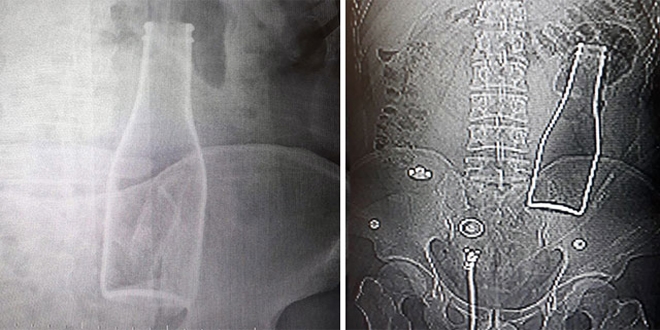

Bunun üzerine röntgen filmi çekilen gencin kalın bağırsağında şişe olduğu görüldü. Makattan girdiği belirlenen şişe, yaklaşık bir saat süren ameliyatla çıkarıldı.

Hastanedeki tedavisinin ardından dün taburcu edilen A.E., polise verdiği ifadesinde, "Olay günü banyoda duş alırken yanlışlıkla bu olay gerçekleşti. Ben de Karaman Eğitim ve Araştırma Hastanesi'ne başvurdum. Yaşanan olaydan dolayı kimseden şikayetçi değilim" diye konuştu.